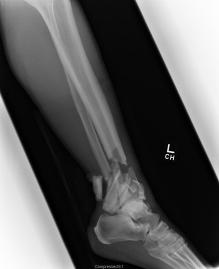

Pre-corrective surgery X-Rays of the damaged right & left legs / ankles

These x-rays were taken at Dr Armendariz’s office, just prior to performing any corrective surgery. As can be seen in these images,

there was no tibia bracing provided by Dr. Keller. Liam was released from Dr Keller’s care with instructions that full weight bearing could

be accomplished within 2 months of Keller’s last surgical procedure. The best example to examine is the second image (from the left) of the

top how. Notice how the bones that should be aligned with the tibia are in fact on the other side of the leg. The third image shows how badly

Liam’s left foot was twisted as a result of the pool placement of the external fixation. What is not obvious is that the screw at the bottom

of the plate on the right fibula missed being screwed into the plate.